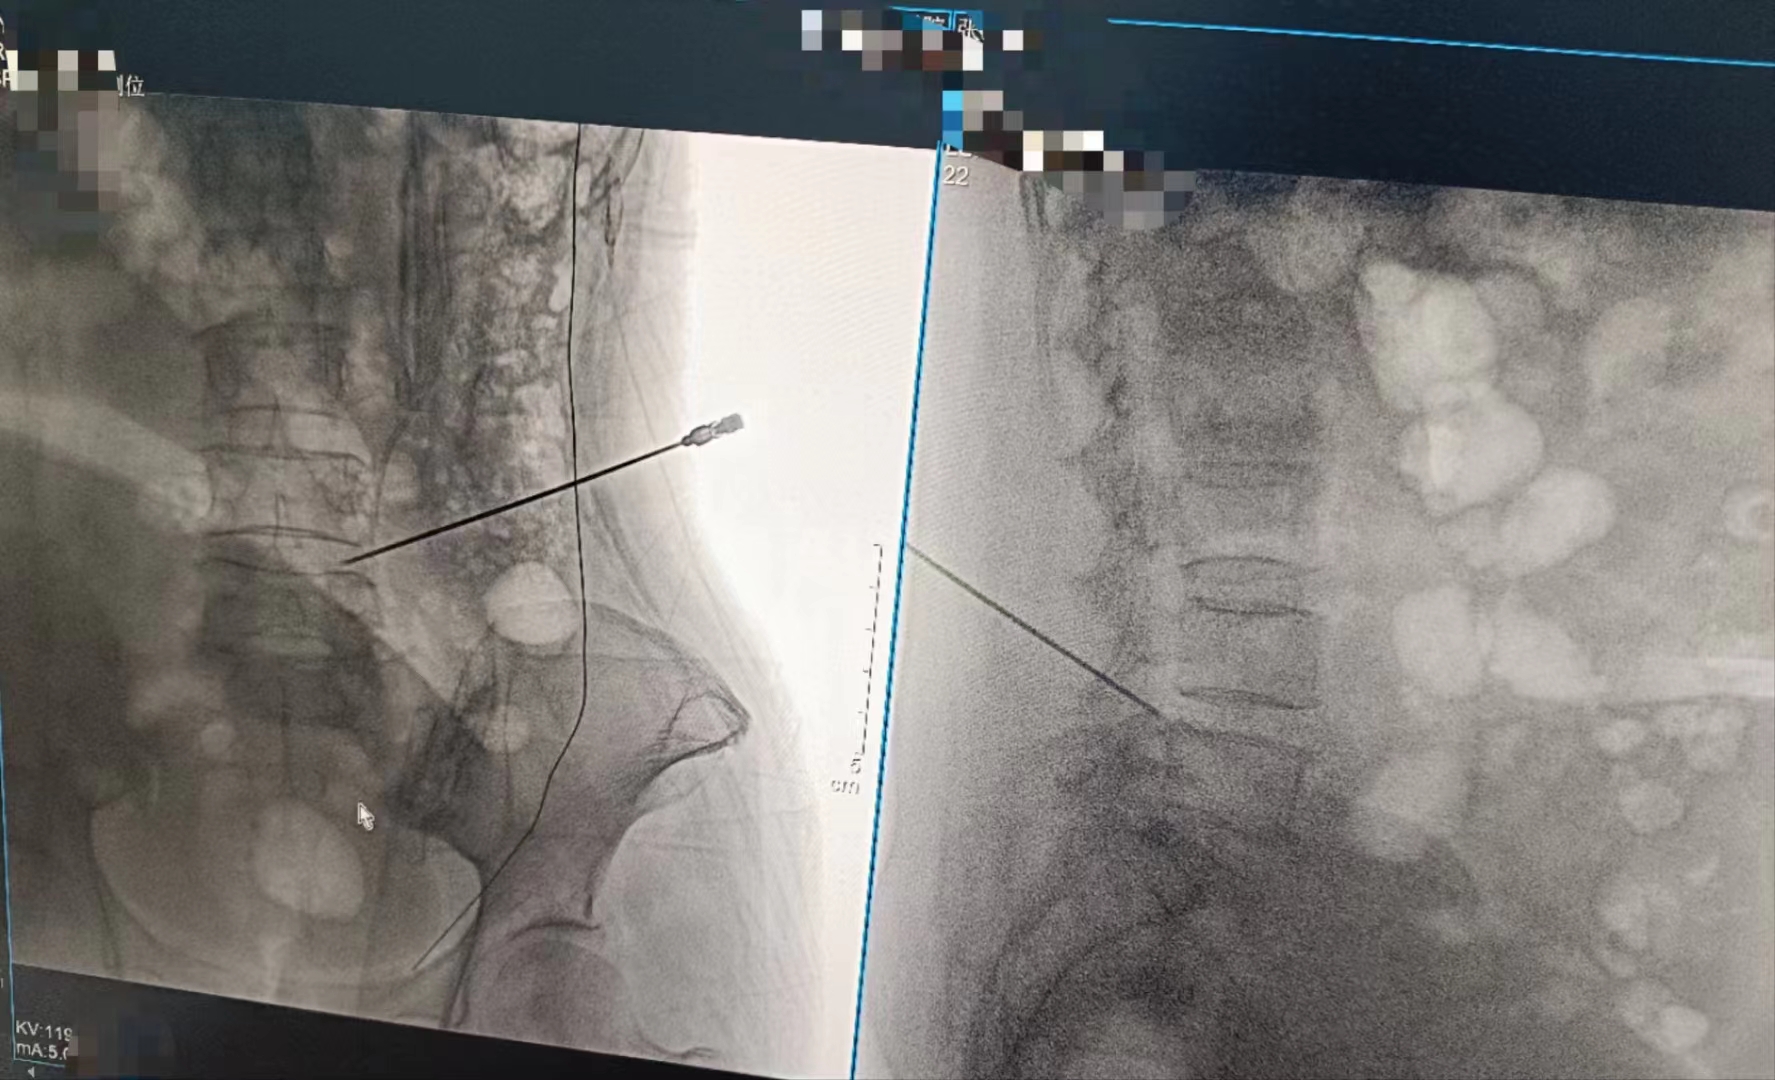

當設備啟動,那束柔和的X射線穿過患者的身體,捕捉下每一個細微的影像。那一刻,時間仿佛凝固,所有的目光都聚焦在那塊屏幕上。那里,生命的紋理清晰可見,疾病的陰影無處遁形。

手術順利完成,當醫生們露出疲憊而欣慰的笑容時,我知道,那不僅僅是勝利的喜悅,更是對生命的敬畏與珍視。而這一切,都離不開這臺數字化X射線攝影設備的默默付出。